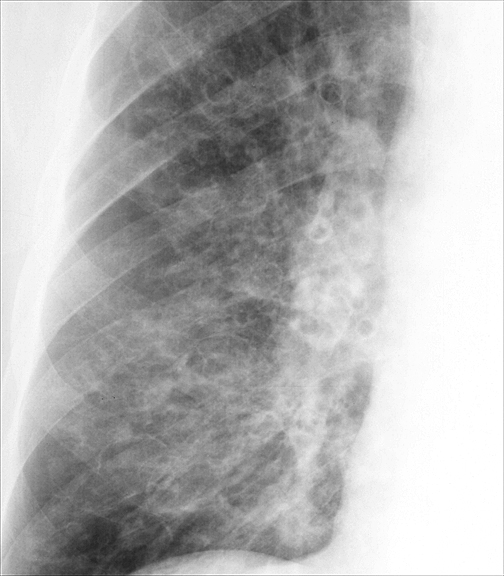

Bronchiectasis

Case 2 PA c/u